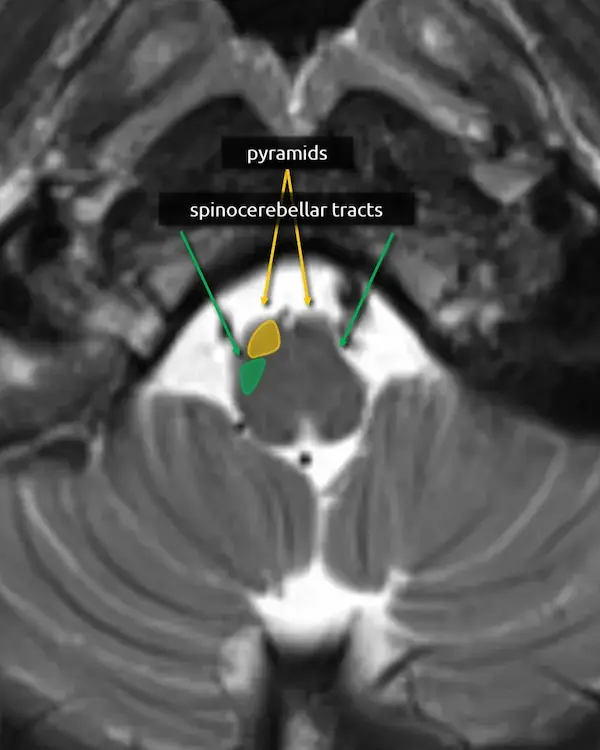

1. Pyramids:

The medullary pyramids contain the corticospinal tract and corticobulbar tract, which are sometimes collectively called the pyramidal tracts. They are named due to the shape they form on the ventral surface of the medulla, which usually becomes more pyramid-like inferiorly.

2. Spinocerebellar tracts:

The spinocerebellar tracts are ascending tracts from the spinal cord to the cerebellum involved in proprioception of the trunk and lower limbs. They are separated into ventral and dorsal divisions; the dorsal division travels to the cerebellum via the inferior cerebellar peduncle and the anterior division goes through the superior cerebellar peduncle. To reach the superior cerebellar peduncle, the anterior spinocerebellar tract travels along the lateral margin of the corticospinal tract through the pons. The spinocerebellar tract is best approximated posterior to the pyramids in the mid to lower medulla, where the ventral and dorsal division remain together.

The upper limb equivalent of the spinocerebellar tract is the cuneocerebellar tract, which is smaller and located medially.

Lesions involving these tracts will cause ataxia.